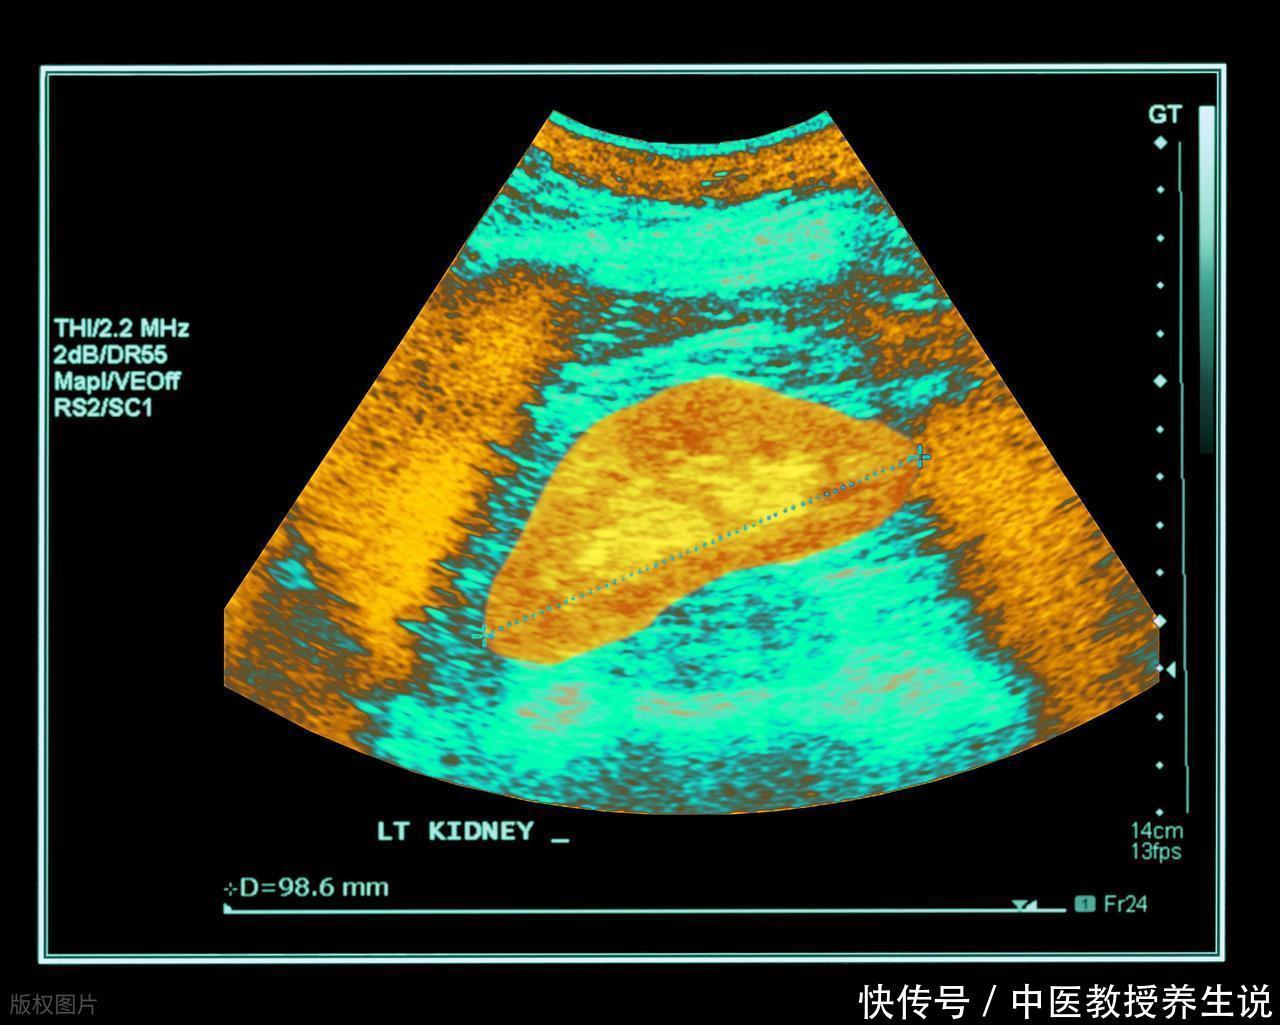

捕捉到上述苗头,并不意味着可以直接给肝结核或任何严重肝病画上等号。这些仅仅是需要专业解读的“原始数据”。将这些信号与真正的诊断混为一谈,无异于看到云就说要下暴雨。影像学检查(如B超)能直观看到肝脏的形态结构,血液里的转氨酶、胆红素等指标则像是肝脏功能的“成绩单”。最终的判断,有赖于医生结合多项证据,进行综合性的鉴别。